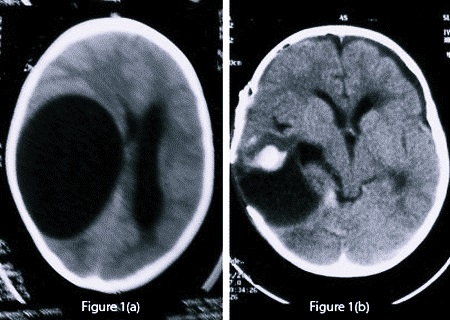

Маленькие по размеру образования обычно отличаются субклиническим течением и поэтому их выявляют совершенно случайно путем нейровизуализирующего обследования головы. Если же киста имеет достаточно большие объемы, то из-за ограниченного интракраниального пространства она может стать причиной развития внутричерепной гипертензии, впоследствии чего произойдет сильное сдавливание соседних мозговых структур.

Специалисты утверждают, что если опухоль обладает клинически незначимыми параметрами, то в большинстве случаев полностью отсутствуют какие-либо из множественных признаков заболевания. Однако при достижении полостью крупных объемов за короткий промежуток времени проявляется характерная клиническая картина, особенности которой определяются локализацией опухоли, силой сдавливания окружающих ее тканей и степенью ухудшения оттока церебральной мозговой жидкости.

Если образование находится в левом полушарии, то без лечения снижаются мыслительные и математические способности, затрудняется чтение и письмо, нарушаются функции правой стороны тела. Постишемическая опухоль может нарушать походку и затруднять передвижение, а в очень сложных ситуациях наступает полный паралич.

Без адекватного лечение кистозное образование в мозгу опасно развитием эпилептических припадков, а у больных с кистой в районе ствола может развиваться дизартрия и дисфагия. Если не обращать внимания на кисту промежуточного паруса, дело может закончиться гидроцефалией, синдромом сдавливания структур мозга или кровоизлиянием. Но самым страшным последствием для любого пациента с кистой в мозгу является внезапная смерть.